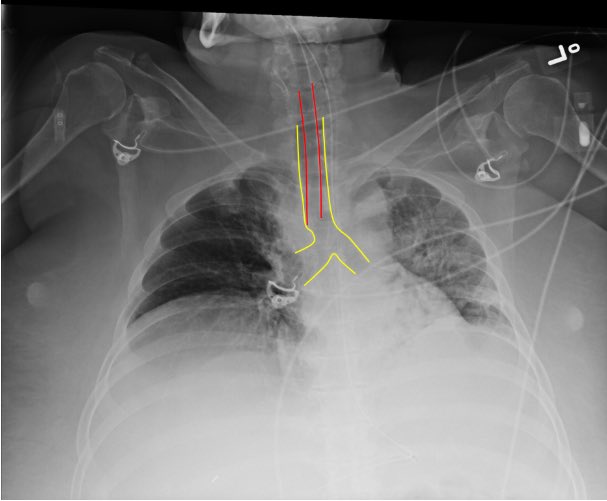

- Is the tube placed appropriately on CXR? (typically 2-5 cm from carina)